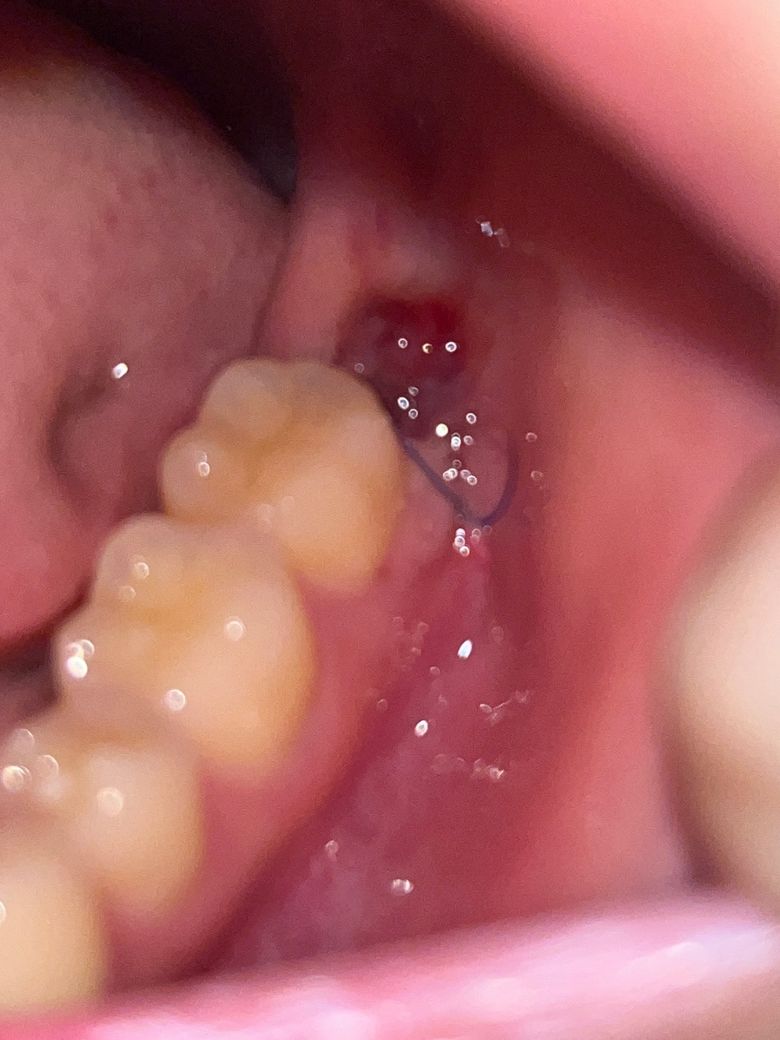

사랑니 발치 4일차인데 피몽우리가 생겼어요

피떡인가요? 떨어질까봐 너무 무서워서 밥도 못먹고 있습니다..

덜렁덜렁 거려서 잘못하면 떨어질것같아요

피떡은 원래 발치한 곳 안쪽에 생기는 거 아닌가요? 왜 이렇게 덜렁거리게 튀어나와있는지 모르겠어요ㅠㅠ

사진으로는 잘 안보이는데 새끼손톱만한 몽우리가 덜렁거려요

발치를 할때 잇몸에 상처가 있다면 사진처럼 보일수 있습니다.

이런 상처는 대부분 문제가 되지는 않기 때문에 걱정하지 않아도 됩니다.

발치를 한부위가 아무는데는 2주정도의 시간이 걸리기 때문에 그동안 해당부위를 자극하지 않는것이 좋습니다.

사진에 보이는건 피가 아니라 잇몸이 치유되면서 생긴 자연스러운 현상이니 너무 걱정하지마세요.

그냥 신경쓰지말고 두시기 바랍니다 피떡은 아닌데 치유 과정에서 생기는 염증, 육아조직입니다